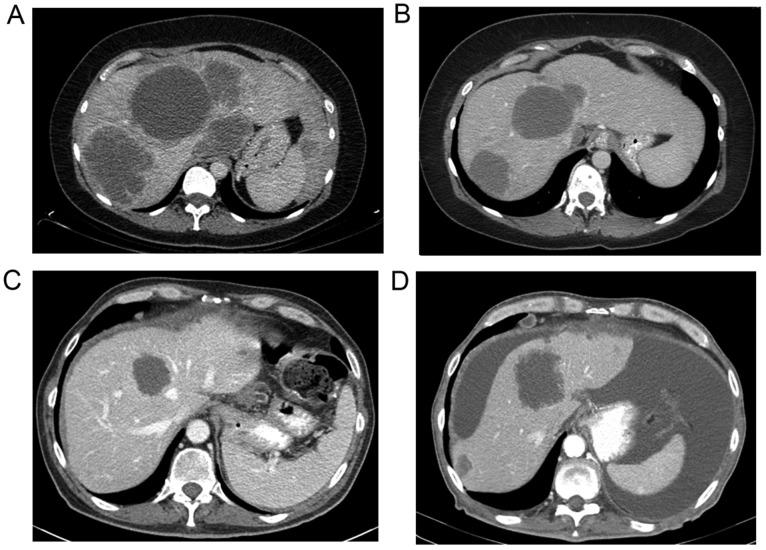

钇-90放射性栓塞治疗KRAS野生型和突变型患者的结直肠癌肝转移:临床和循环游离DNA研究

Yttrium-90 radioembolization for colorectal cancer liver metastases in KRAS wild-type and mutant patients: Clinical and ccfDNA studies.

Patients with unresectable, chemo-refractory colorectal cancer liver metastases (CRCLM) have limited local treatment options. We report our institutional experience on the efficacy of resin-based yttrium-90 (90Y) radioembolization for the treatment of CRCLM and our findings on associated circulating cell-free DNA (ccfDNA) studies. A total of 58 patients treated with 90Y for CRCLM at the Medstar Georgetown University Hospital had a median survival of 6 months [95% confidence interval (CI), 4.55‑7.45 months] after treatment, with a 12-month survival rate of 33%. The median survival from treatment stratified by mutational status was longer in the wild-type (WT) as compared to the KRAS mutant patients at 7 vs. 5 months, but did not achieve statistical significance (p=0.059). Median tumor local control duration after 90Y treatment was 2 months (95% CI, 0.34‑3.66 months) for the entire cohort and was longer in the WT vs. the mutant patients (2 vs. 1 month, respectively, p=0.088). Plasma was prospectively collected from a subset of 9 patients both before and after single lobe treatment, and ccfDNA concentration and fragmentation index (FI) were measured using quantitative PCR and atomic-force microscopy (AFM). In the WT and KRAS mutant patients, DNA FI was reduced from a median of 0.73-0.65 after treatment. A reduction in DNA FI after single lobe treatment was associated with an improved overall survival (p=0.046). Analysis by AFM of paired pre- and post-treatment samples from KRAS mutant and WT patients revealed a larger average decrease in fragment size in the WT patients (p=0.013). 90Y radioembolization extends local control for CRCLM, however, KRAS mutant tumors may be more radio-resistant to treatment. Changes in the FI of patients following treatment were noted and may be evaluated in a larger study for relevance as a biomarker of response.

不可切除的化疗难治性结直肠癌肝转移(CRCLM)患者的局部治疗选择有限。我们报告了我们机构关于基于树脂的钇-90(90Y)放射性栓塞治疗CRCLM的疗效以及相关循环游离DNA(ccfDNA)研究的结果。在梅斯达乔治敦大学医院,共有58例接受90Y治疗的CRCLM患者在治疗后的中位生存期为6个月[95%置信区间(CI),4.55 - 7.45个月],12个月生存率为33%。按突变状态分层的治疗后中位生存期,野生型(WT)患者(7个月)比KRAS突变型患者(5个月)长,但未达到统计学意义(p = 0.059)。整个队列90Y治疗后的中位肿瘤局部控制持续时间为2个月(95% CI,0.34 - 3.66个月),WT患者比突变型患者更长(分别为2个月和1个月,p = 0.088)。前瞻性收集了9例单叶治疗前后患者的血浆,并使用定量PCR和原子力显微镜(AFM)测量ccfDNA浓度和片段化指数(FI)。在WT和KRAS突变型患者中,治疗后DNA FI从中位值0.73降至0.65。单叶治疗后DNA FI的降低与总体生存期改善相关(p = 0.046)。对KRAS突变型和WT患者治疗前后配对样本进行AFM分析显示,WT患者片段大小的平均减小幅度更大(p = 0.013)。90Y放射性栓塞可延长CRCLM的局部控制时间,然而,KRAS突变型肿瘤可能对治疗更具放射性抗性。注意到治疗后患者FI的变化,可能需要在更大规模的研究中评估其作为反应生物标志物的相关性。